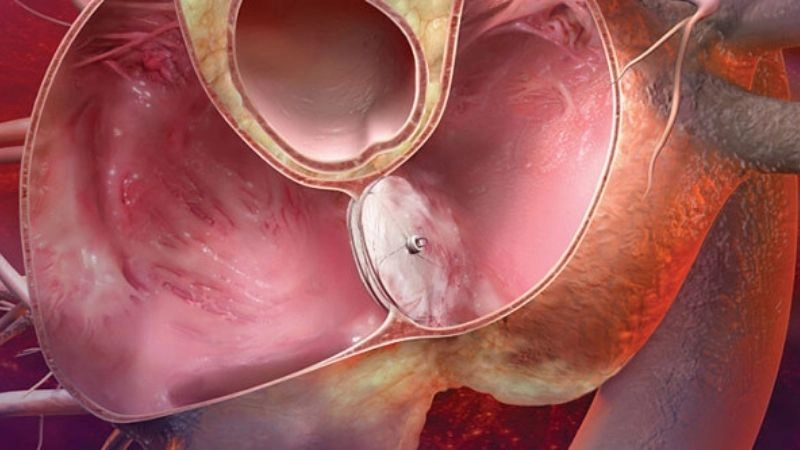

Patent foramen ovale is a heart condition where a small flap-like opening between the left and right atria fails to close after birth. Visual examples often show its location within the atrial septum and how blood flow may bypass normal circulation.

Patent foramen ovale closure procedure to seal heart opening

Patent foramen ovale surgery repairing congenital heart hole